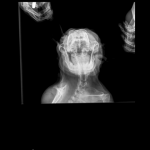

Французский бульдог,6 лет.Стала плохо ходить,что- то с позвоночником.Врачи не могут поставить диагноз.Есть снимки.Помогите!

Можете приложите к следующему комментарию снимки, я их посмотрю. Хотя, если бы на них были изменения, то Ваши врачи их бы увидели.

Снимки хорошие, качественные, но совершенно не информативные. На этих пленках патология не определяется. Но здесь нет снимка, который нужен обязательно - поясничный отдел позвоночника в прямой проекции (такой, как 3-й, но только не шея, а поясница).

Нет,наоборот.Собака сначала стала немного наклонять голову вправо.Когда были на консультации у окулиста,то он обратил внимание на это ,сказал,что есть какие-то изменения в области шеи.Я отсутствовала дома 2 недели.Приехала,собаку вообще не узнала.Крен головы вправо стал еще сильнее,передние ноги как-то ослабли.Она идет,может споткнуться,упасть.Сходили,сделали рентген.снимок.Поставили диагноз:атланто-аксиальная нестабильность шейного отдела,спондилоартроз. Проколола 5 дней:актовегин,папаверин,комбилипн,мидокалм,дексаметазон. Пока делала уколы и еще дней 5 после этого собаке стало легче,а потом опять вернулись к тому, что было.На консультации врач сказал,что дальше просто колоть преднизалон. Я уехала к другому врачу,тот сделал снимки,которые я Вам отослала.Сказал, что диагноз не подтверждает,на пальцах показал, что со спинным мозгом все нормально.С помощью какой-то процедуры (бумаги на работе)обнаружил перфорацию барабанной перепонки.Выписал лечение:цефтриаксон,циклоферон,цебролизин(колола 2 дня,стало хуже),комбилипен.В уши-изотик.Сказал,что может быть у собаки был инсульт.Собаке от лечения хуже.Вот такие дела.